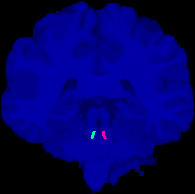

Locus Coeruleus Manual Labels for 20 HCP Subjects Images

1 Images available.

Description:Manually annotated locus coeruleus labels